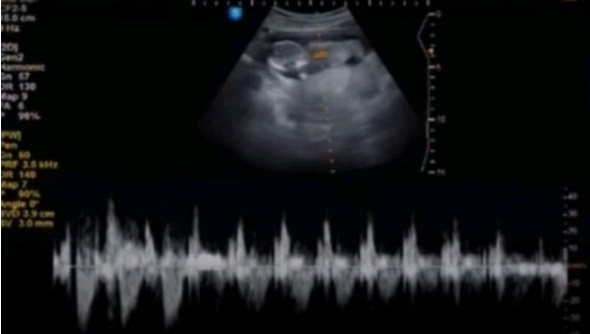

임신7주 증상, 처음으로 심장소리를 들었어요 :)

안녕하세요 쪼꼬미입니다 저번주까지는 정말 날씨가 딱 좋았는데 이번주는 왜이렇게 추운걸까요ㅠ_ㅠ 정말 ...